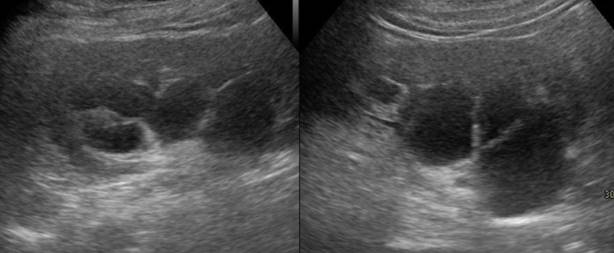

Se le realizó ecografía abdominal (►Fig. 1), que evidenció riñones de tamaño levemente aumentados, con aumento difuso de la ecogenicidad cortical, y en ambos senos renales dilataciones quísticas multitabicadas, de paredes finas, bien definidas. Se decidió complementar estudio con Uro-Tomografía Computada (TC) (►Fig. 2), donde se objetivaron riñones de tamaño levemente aumentado a expensas de numerosos quistes peri-pélvicos bilaterales, de paredes finas, bien definidas, que producen compresión extrínseca del sistema colector, con dilatación proximal secundaria.

La ultrasonografía evidencia colecciones peripiélicas, perirrenales o intrarrenales uni o multiloculares con septos y ecos en su interior en los casos de detritus y hemorragia.1,5 La TC muestra colecciones hipodensas perirrenales y/o en el seno renal, que varían entre 0 y 15 UH (siendo de mayor atenuación en los casos de hemorragia), y sin refuerzo luego de la administración de contraste. Las fases tardías frecuentemente muestran compresión de la pelvis y cálices por los quistes en el seno renal. La corteza renal habitualmente es normal, pero puede estar adelgazada debido a la compresión extrínseca. La resonancia magnética (RM) muestra colecciones hipointensas ponderadas en T1 e hiperintensas ponderadas en T2.1,2,4,5 La falta de comunicación entre el componente quístico renal y el sistema pielocalicial en la fase excretora de TC o RM con contraste sugieren el diagnóstico de linfangiectasia.4